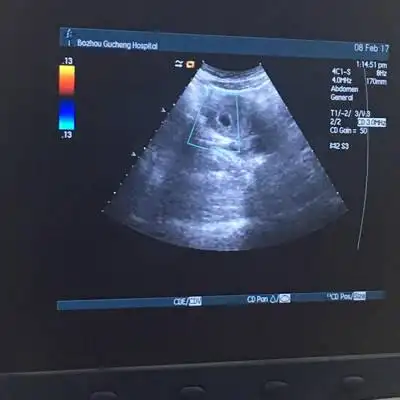

别人说孕囊是白色

有妇产科医生帮忙看看这是完整孕囊吗?

怀孕40天有很小的红色血块流出,查b超显示有孕囊,是先兆流产吗?

各位宝妈帮我看一下,这个是孕囊吗?

请问排出的这是孕囊吗?